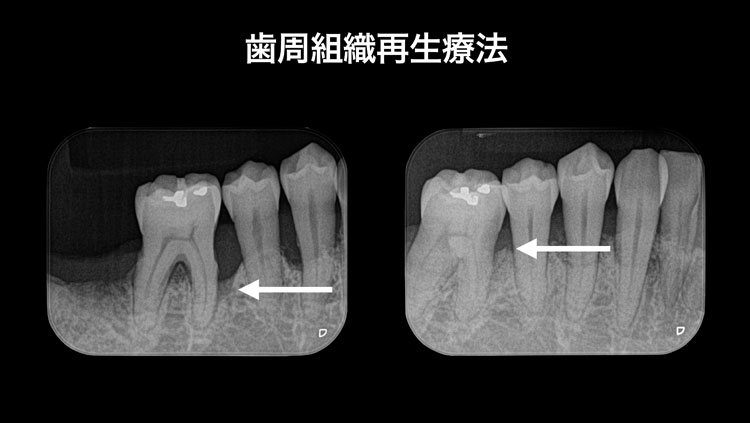

歯周組織再生療法

過去において重度歯周炎は保存不可能でした。なぜなら、歯周治療のゴールは歯周病の進行を止めることであり、健康な状態に戻すことではありませんでした。歯周炎が進行してしまい歯を支える骨がなくなってしまうと進行を止めたとしても歯として機能することができません。歯周組織再生療法においては歯を支える骨を増やすことができるため重度歯周炎の歯であっても保存が可能になりました。